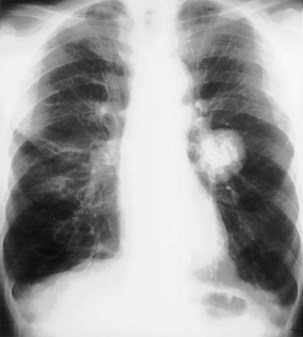

Density

Most pulmonary masses are of soft tissue density. However, careful inspection must be made for the presence of calcification, because certain patterns of calcification are typical of benign lesions that may be safely observed rather than resected (Figure 7-51). A completely or centrally calcified nodule is diagnostic of a tuberculoma or histoplasmoma. Often, CT is required to confirm this pattern of calcification. Likewise, concentric rings of calcification are typical of healed histoplasmosis infection. Popcorn calcification, within the matrix of a pulmonary nodule, is highly suggestive of a hamartoma (Figure 7-52). Other forms of calcification do not reliably indicate whether a nodule is benign or malignant, and dystrophic calcification within a pulmonary malignancy is relatively common.